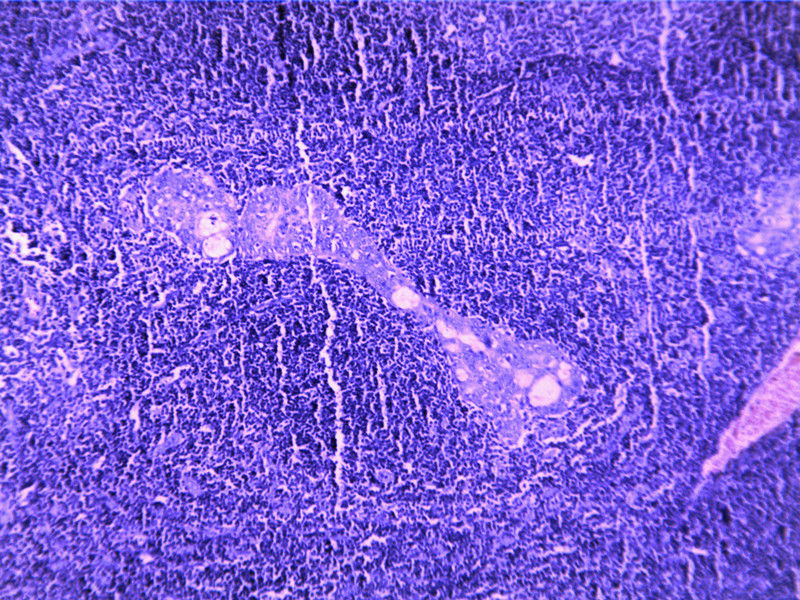

要想Hold住这个肿物的病理诊断,需要了解:

3)该标本到底是不是靠近腮腺表面的淋巴结?

4)3cmX2.5cmX2.5cm的肿块虽然大体上显示界清,那镜下的边界到底清不清?

需要鉴别的肿瘤:

(1)皮脂腺淋巴腺瘤

(3)良性淋巴上皮病

(4)粘膜相关淋巴组织淋巴瘤(MALT淋巴瘤)